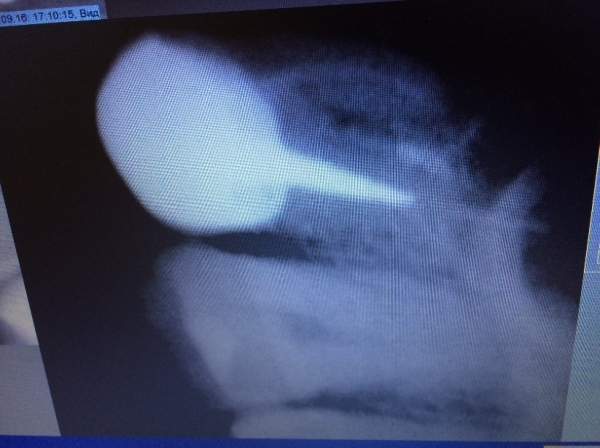

Сутки назад поставил коронку на живой зуб (жевательный снизу), до установки коронки зуб не болел. До установки пломба была большой и отвалилась часть стенки зуба, врач-стоматолог посмотрел снимок и сказал, что лучше ставить на живой зуб, так как воспалений и всяческих патологий нет, зуб лучше сохранить, коронка цирконий!

После установки коронки ноет зуб, ныл и после обточки, нормально ли это? Боль ноющая, есть реакция на холод и горячее, периодически затихает, при надавливании на зуб есть болевое ощущение. Есть ли восстановительный период?

Такое случается, но острой боли быть не должно. Скорее всего, чувствительность не пройдет, а будет усиливаться, так как при обточке зуб уже реагировал на внешние факторы. Покажитесь врачу, сделайте рентген и картина будет ясна.